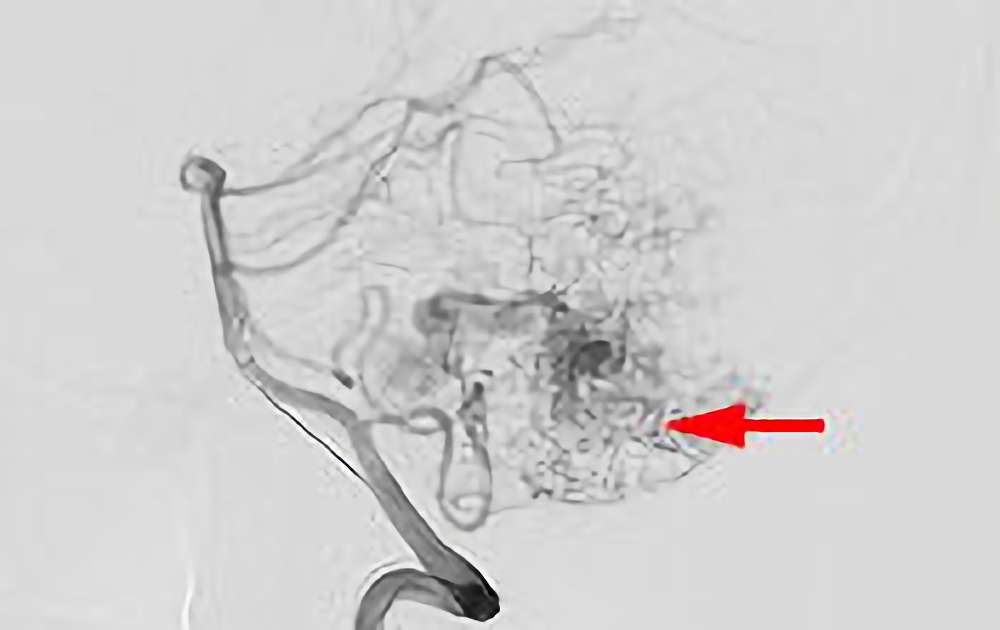

'25年10月

脳動静脈奇形

50代

大阪府の病院

No.1585 手術前

No.1585 手術中

No.1585 手術後